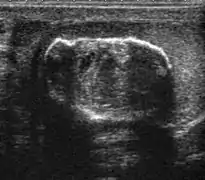

Embryonal cell carcinomas, a more aggressive tumor than seminoma usually occurs in men in their 30s. Although it is the second most common testicular tumor after seminoma, pure embryonal cell carcinoma is rare and constitutes only about 3 percent of the nonseminomatous germ cell tumors. Most of the cases occur in combination with other cell types. At ultrasound, embryonal cell carcinomas are predominantly hypoechoic lesions with ill-defined margins and an inhomogeneous echotexture. Echogenic foci due to hemorrhage, calcification, or fibrosis are commonly seen. Twenty percent of embryonal cell carcinomas have cystic components. The tumor may invade into the tunica albuginea resulting in contour distortion of the testis [Fig. 4].